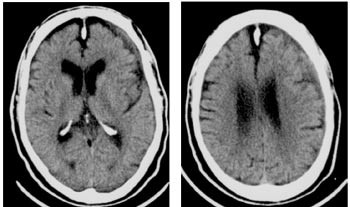

Pasienten ble overflyttet til regionsykehus, der det neste dag ble foretatt evakuering av kronisk subduralt hematom. Det ble anlagt to borehull, og i begge tømte det seg væske under høyt trykk. Forløpet var ukomplisert, pasienten var oppegående og kjekk og ble utskrevet til hjemmet fem døgn postoperativt med beskjed om ikke å ta acetylsalisylsyre de neste to ukene. Ti døgn senere (15 døgn postoperativt) ble han reinnlagt. Han klaget igjen over at høyre hånd ikke lystret ham, og fastlegen mente dessuten at han var mentalt tregere enn vanlig. Komparentopplysninger fra hans samboer indikerte at han hadde vært betydelig bedre kort etter operasjonen, men så var blitt dårligere. Ved undersøkelsen kunne man få inntrykk av en noe redusert nærhukommelse. Han lette etter ordene, og det var tydelig temporeduksjon i høyre sides arm og bein samt klossethet for finere fingerbevegelser på høyre side. Videre ble det bemerket lett redusert sensibilitet og noe livligere dype senereflekser på høyre side. Ny cerebral CT-undersøkelse (fig 2) viste en venstresidig subdural effusjon av nærmest uendret størrelse, men det var nå oppstått ulik røntgentetthet (sjiktning) i væsken som uttrykk for mulig reblødning.

I løpet av de neste dagene falt han flere ganger, var tung å få opp, og var periodevis tydelig forvirret. Det ble gjort ytterligere en CT-undersøkelse 24 døgn etter den andre operasjonen. Bildet var nærmest identisk med det som var tatt før den andre operasjonen (fig 2), og viste fremdeles et stort subduralt hematom med sjiktning og overskyting av midtlinjestrukturer. Det ble igjen tatt kontakt med nevrokirurgisk avdeling, som opprettholdt vurderingen av at ny operasjon ikke var indisert. Etter ytterligere fire døgn kom det imidlertid kontrabeskjed. For tredje gang ble det utført evakuering av kronisk subduralt hematom, sju uker etter den første operasjonen og fire uker etter den andre.